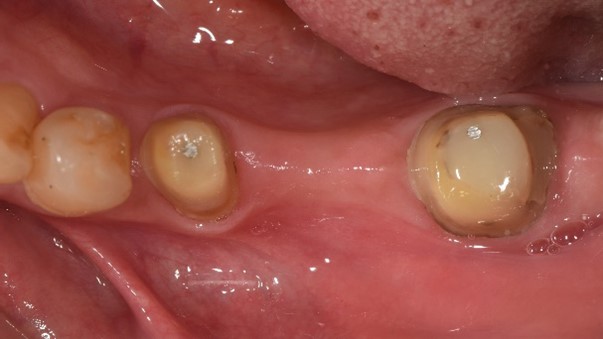

案例:蓄意再植

原先病人做牙橋的大臼齒因為牙根發炎,疼痛難耐,前來做根管治療,但因為大臼齒牙根末端神經較複雜、且有張口困難的問題,因此更增加了做根管治療的困難度,在經醫師評估後,建議做蓄意再植手術。

治療前:蛀牙嚴重、牙根發炎。